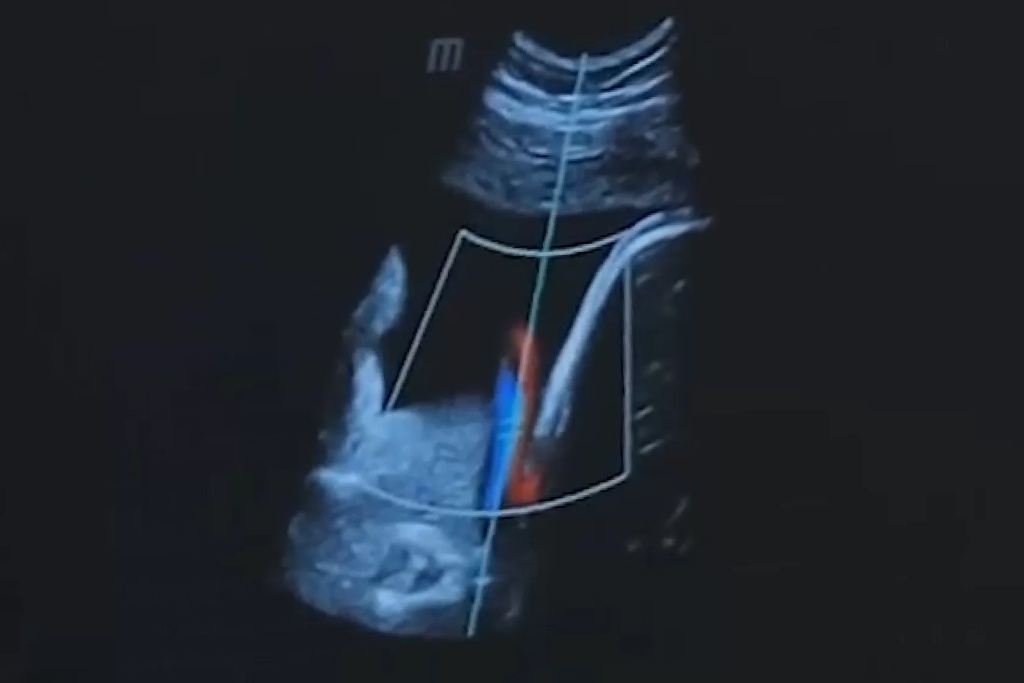

В кардиологии режим тканевой гармоники активно используется для более точной оценки функции сердца и выявления структурных изменений в миокарде. Это содействует более эффективной диагностике и планированию лечения сердечно-сосудистых заболеваний.

В случае кардиологии, тканевая гармоника позволяет детально изучать состояние сердечной мышцы, обеспечивая более точную оценку функциональных изменений. Это имеет важное значение при выборе оптимального лечения сердечно-сосудистых заболеваний.